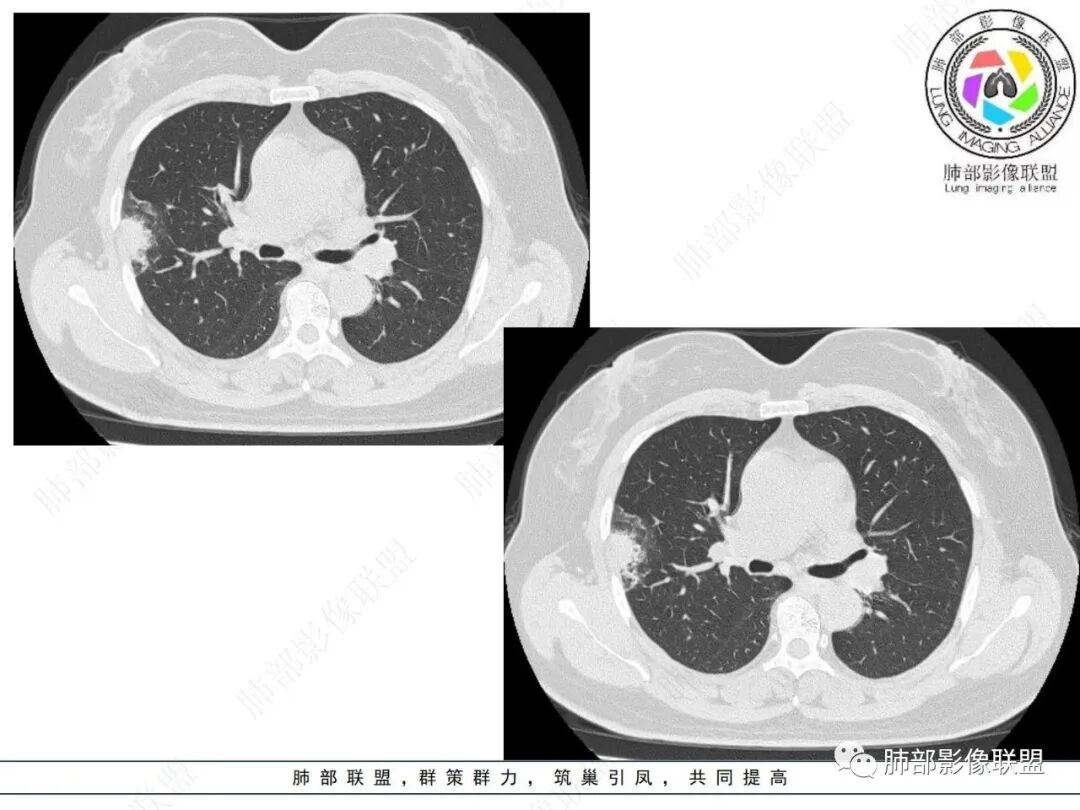

右肺上叶胸膜下混合磨玻璃团片影。

周围磨玻璃部分间杂条索状高密度区,密度欠均匀(可疑重力分布趋势),其磨玻璃影边界大多较清楚或可分辨,部分“L型”边缘,提示小叶间隔阻挡可能。血管穿行自如,可疑远端支气管进入。

实性部分较密实,不规则,隐约见棘突或刺状突起,未见钙化、空洞或液化区,实性边缘可见斑状略低密度间隙(借用王兆宇老师课件,称其呈“松软”的形态)。动脉期实性部分较明显不均匀强化,如果有完整增强图,还可以观察内部血管情况。

纵隔窗相对肺窗病灶相对小,仅部分实性影呈现。病灶张力不高,相邻胸膜增厚(糊墙),未见明显胸膜牵拉凹陷。

右肺上叶胸膜下混合磨玻璃结节,磨玻璃部分与实性部分密度都不均匀,病灶有重力分布效应,小叶间隔阻挡,收缩力羸弱。中老年女性,如此大范围病灶,缺乏临床表现,会让人警惕非感染性病变,尤其是恶性病灶可能!

病灶磨玻璃部分边界较清楚,有重力分布趋势,可能会想到黏液腺癌,或者分泌粘液的腺癌的可能性。不支持地方也有,如实性部分密度偏高,病灶强化程度偏高等。